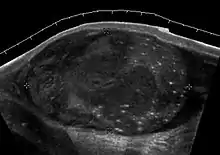

Teratoma Although teratoma is the second most common testicular tumor in children, it affects all age groups. Mature teratoma in children is often benign, but teratoma in adults, regardless of age, should be considered malignant. Teratomas are composed of all three germ cell layers, i.e. endoderm, mesoderm and ectoderm. At ultrasound, teratomas generally form well-circumscribed complex masses. Echogenic foci representing calcification, cartilage, immature bone and fibrosis are commonly seen [Fig. 5]. Cysts are also a common feature and depending on the contents of the cysts i.e. serous, mucoid or keratinous fluid, it may present as anechoic or complex structure [Fig. 6].

- Fig. 5. Teratoma. A plaque-like calcification with acoustic shadow is seen in the testis.

- Fig. 6. Mature cystic teratoma. (a) Composite Image. Mature cystic teratoma in a 29-year-old man. Longitudinal sonography image of the right testis shows a multilocular cystic mass. (b) Mature cystic teratoma in a 6-year-old boy. Longitudinal sonography of the right testis shows a cystic mass containing calcification with no obvious acoustic shadow.